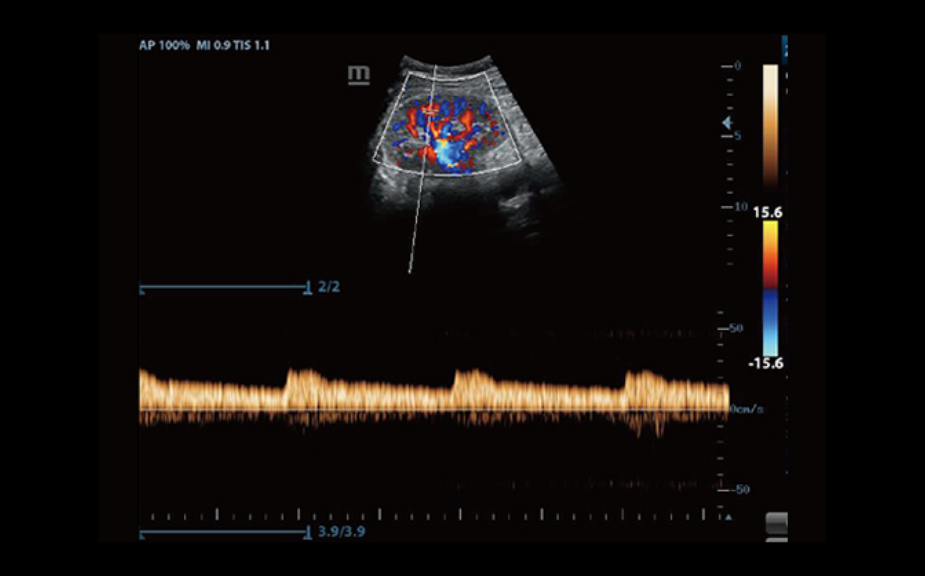

3B/4B G?rÞntÞleme

G?rÞntÞnÞn her y?nden h?zl? ve kolay bir ?ekilde izlenebilmesini sa?layan 3B/4B ?evirme ve E?itleme ?zelli?i ile